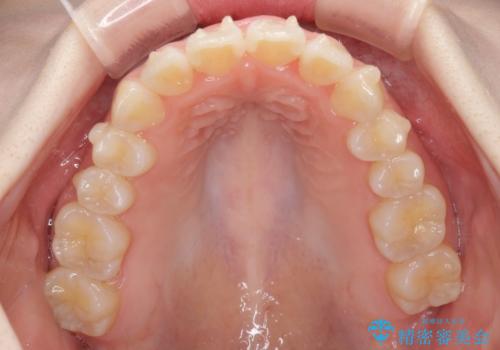

- 前歯の捻れと、ちょっとした出っ張りを気にして来院された患者様です。

歯と歯の間を削る(IPR)ことでデコボコを解消し、インビザラインで整えることとしました。

インビザライン治療特有の奥歯が接触しない時期が続き、当初予定よりも期間がかかりましたが、最終的には安定した咬み合わせと、整った前歯になりました。